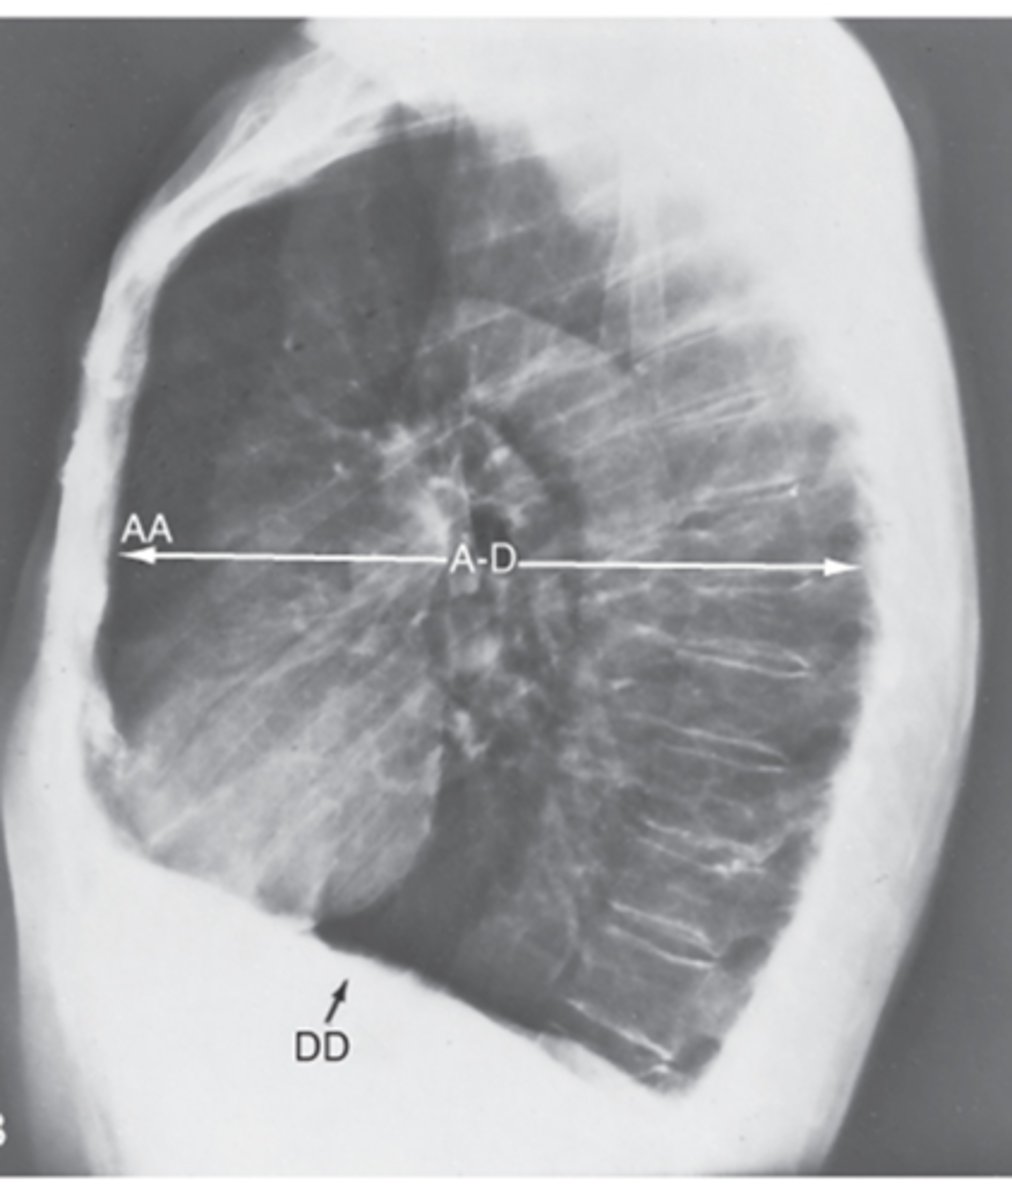

Hyperinflation of the lungs from obstructive lung disease (increased AP diameter and flattening of diaphragm)

Interpretation?